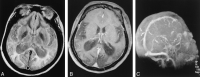

MR images and time-of-flight MR venogram of the brain. A, Axial proton density-weighted (6200/105/1 [TR/TE/NEX]) MR image reveals normal flow voids in the straight sinus and sagittal sinus. B, Contrast-enhanced T1-weighted (414/17/1) image reveals normal flow in the venous sinuses. C, Time-of-flight MR venogram (30/6) shows normal flow in the straight sinus and superior sagittal sinus.